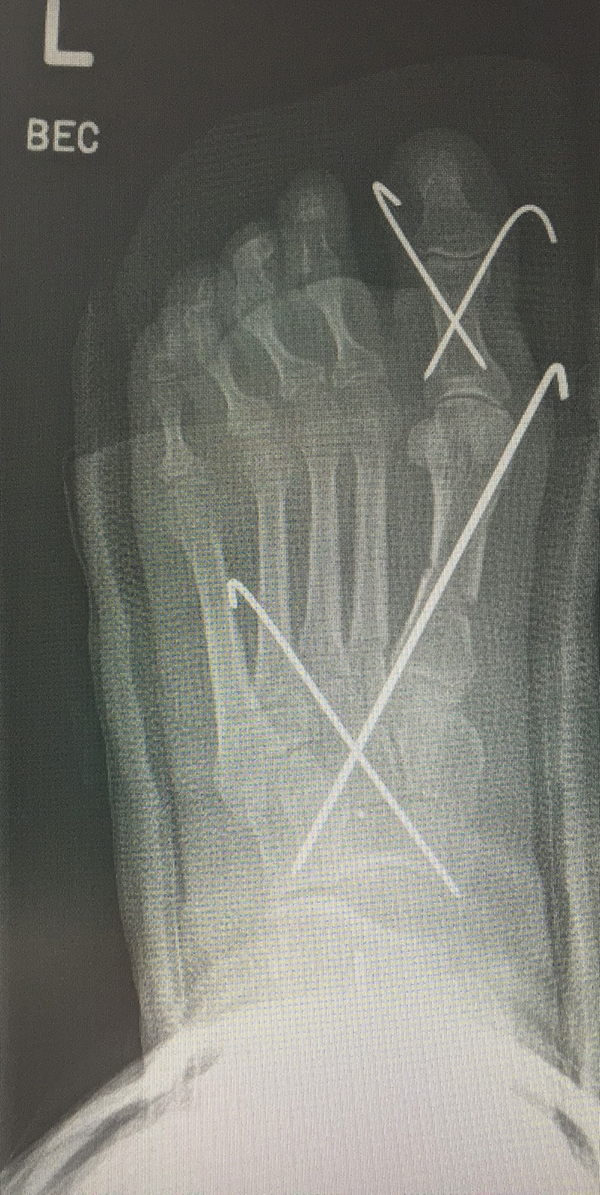

Werden komplette Osteotomien an den Zehen durchgeführt, fädeln wir die Osteotomien mit einem 1.2 oder 1.4 mm Kirschner-Draht auf, damit die einzelnen Fragmente nicht verkippen (Abb. 22).

Abb. 22 a-d: Präoperative Klauenzehen beim Jugendlichen in zwei Ansichten (a-b) und postoperative Auffädelung mit Kirschner-Drähten linker und rechter Fuß (c-d).